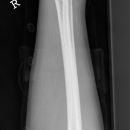

Grünholzfraktur

Nichtdislozierte Grünholzfraktur